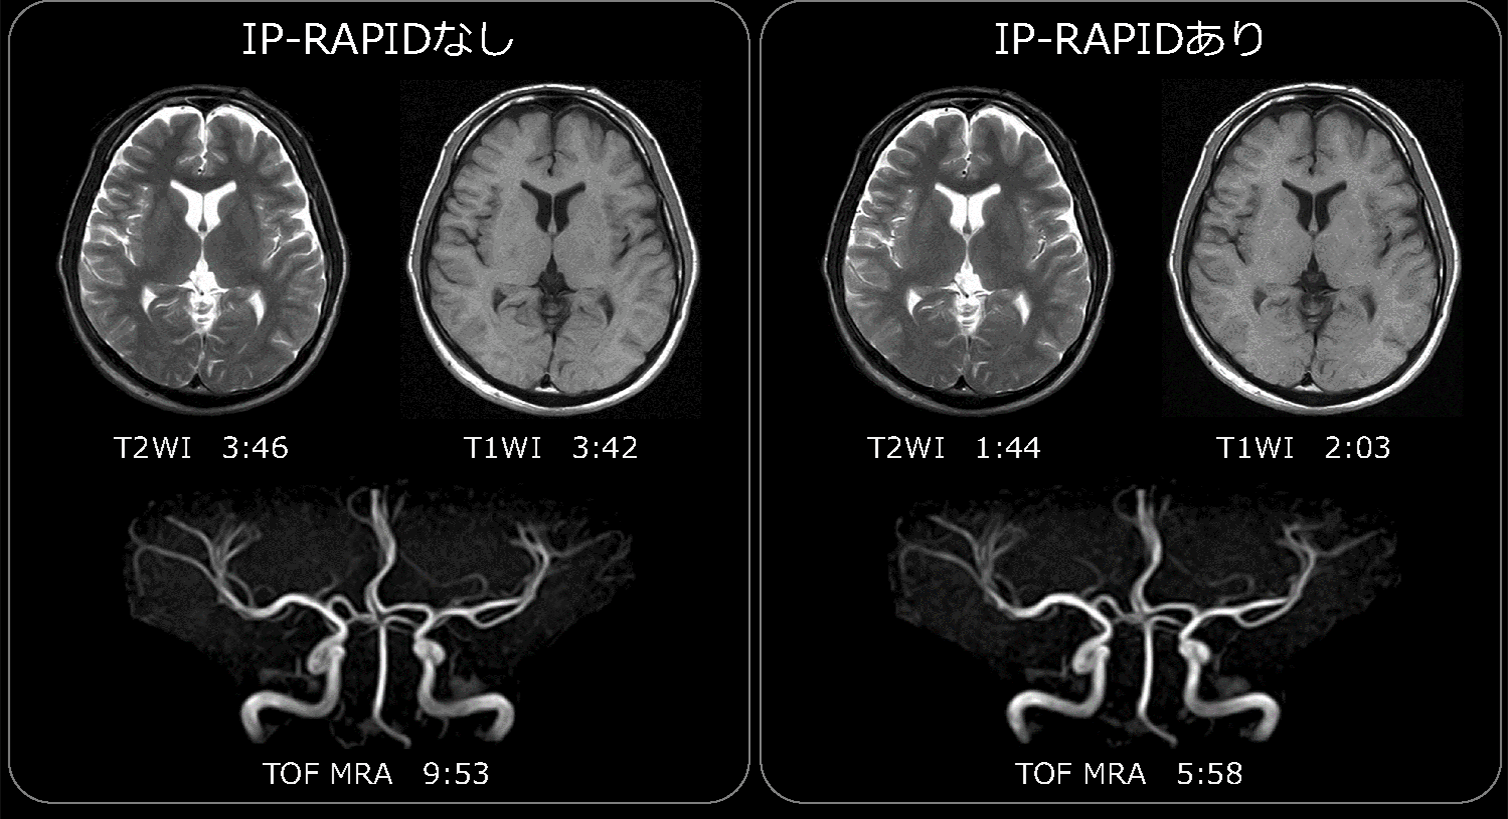

IP-RAPIDの撮像時間短縮効果を確認するために、1.5T MRI装置で撮像した頭部画像にIP-RAPIDを適用した。図4に、IP-RAPID非適用時のルーチンプロトコルと、IP-RAPIDを適用して撮像時間を短縮したプロトコルで撮像した画像をそれぞれ示す。図4に示すように、IP-RAPIDを適用することで、画質の低下なくプロトコル全体の撮像時間が半減していることがわかる。また、IP-RAPIDは、FSE法だけでなく、スピンエコー法(SE)やグラディエントエコー法(GrE)のほか、拡散強調画像(DWI)、3D TOF-MRA(Time-of-Flight MR Angiography)などさまざまな撮像シーケンスに適用でき、撮像時間の短縮に効果があることがわかる。

図4 頭部ルーチンプロトコルにおけるIP-RAPID有無の比較(磁場強度1.5T 超電導MRI)

IP-RAPIDを適用することにより、撮像時間が半分以下となっても、IP-RAPID非適用時と同程度の画質が得られている。